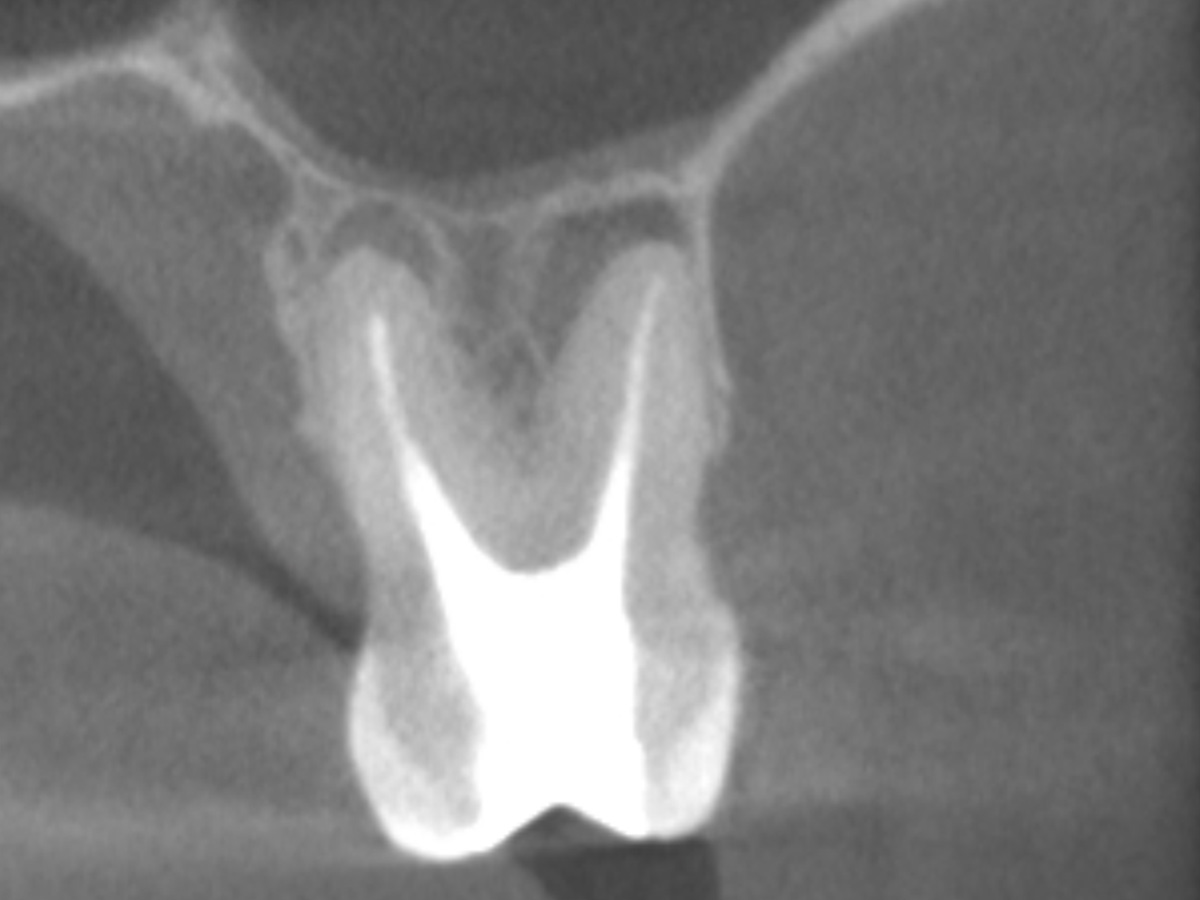

Der Patient stellte sich mit Aufbissschmerzen vor, wobei die klinische und röntgenologische Untersuchung eine symptomatische apikale Parodontitis an einem bereits wurzelkanalbehandelten Zahn 26 ergab. Die DVT-Aufnahme deutete auf einen unbehandelten zusätzlichen Kanal in der mesio-bukkalen Wurzel hin. Die Darstellung und Behandlung des mb2s sowie die Revision der bereits behandelten Kanäle erfolgte mit dem XP-endo® Rise Shaper bei einer hohen Umdrehungszahl von 2.500rpm.

Abbildung 1

DVT axial